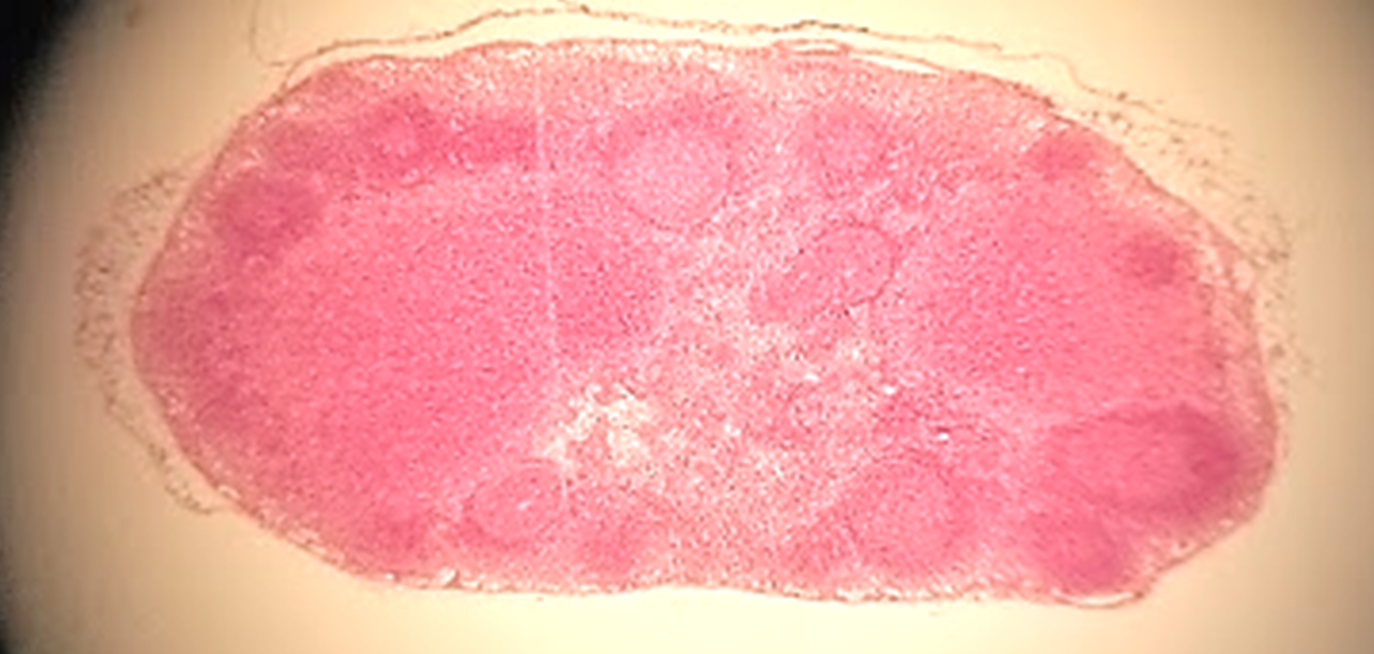

lymph node

what is this a sample of?

medulla of lymph node

what is outlined?

cortex of lymph node

follicle no germinal center

follicle germinal center